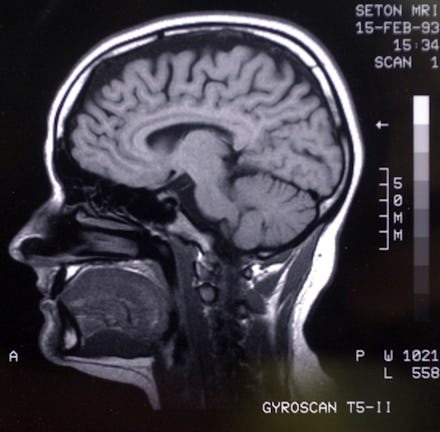

Separating the go-getter from the people person. "I felt that those differences must also be present, to some extent, in the brain," White said. To test this theory, she and her co-author Erica Grodin from the National Institutes of Health examined a number of brain scans and found that these two types of extroverts do, in fact, have different brains.

White and Grodin examined 83 brain scans from people with a range of personality traits, not all of whom were extroverted. The team then compared the scans of those on the self-reported agentic side with those on the self-reported affiliative side and found a discernible difference.

It's all a gray matter. In the scans, the researchers noticed a difference in regional concentrations of gray matter, the brain's outer layer made up of neurons that help process sensory information and deliver nutrients to help the brain fire signals.

So to speak, the more gray matter you have in a given region of your brain, the better that region will work to keep your senses sharp.

People who scored higher on the agentic extraversion measure had greater gray matter in specific regions of the brain as well as the medial orbitofrontal cortex (a small region that sits between the eyes), Grodin explained. People who scored higher on affiliative extraversion also showed increased gray matter in the medial orbitofrontal cortex but not in any other regions.

The team found exactly what they had hoped for: a distinct anatomical difference in the brains of the agentics and the affiliates. Based on past research, it makes a lot of sense.

A 2012 study found introverts have more gray matter in their prefrontal cortex, the region of the brain that helps control thinking and decision making. Another paper found extroverts have more active dopamine receptors and are more sensitive to the social rewards. In a similar way, agentic extroverts may have more gray matter in regions of the brain that are stimulated by rewards than their affiliate counterparts.